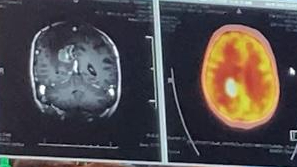

I’m feeling quite tired this afternoon, so I’ll just end with the message Dave sent out after my recent PET CT scan to look into the problems with my left side:

Hi all, we have had some troubling news. It seems the tumor in the back of Dawn’s brain is growing again. This is not a major surprise due to the type of cancer. We just discussed this with the Dr. and there are a few options that the Dr. is suggesting. First is sending a thin probe into the tumor area for an ablation, where they burn out the tumor in a controlled way. There is a new chemo drug we can try, and a trial that Dawn can enter. Also, more invasive surgery. The Dr. is working through the options, currently the favored options are a referral for the ablation procedure and entering the trial. The other benefit of the ablation is that it opens up the blood brain barrier to make the trial and / or other chemo drugs more effective. Not good news but we continue to be positive and hope for the best in further treatment. Dawn is basically okay in herself and starting to make improvements from the swelling.

https://www.cancercenter.com/diagnosing-cancer/diagnostic-imaging/pet-ct-scan